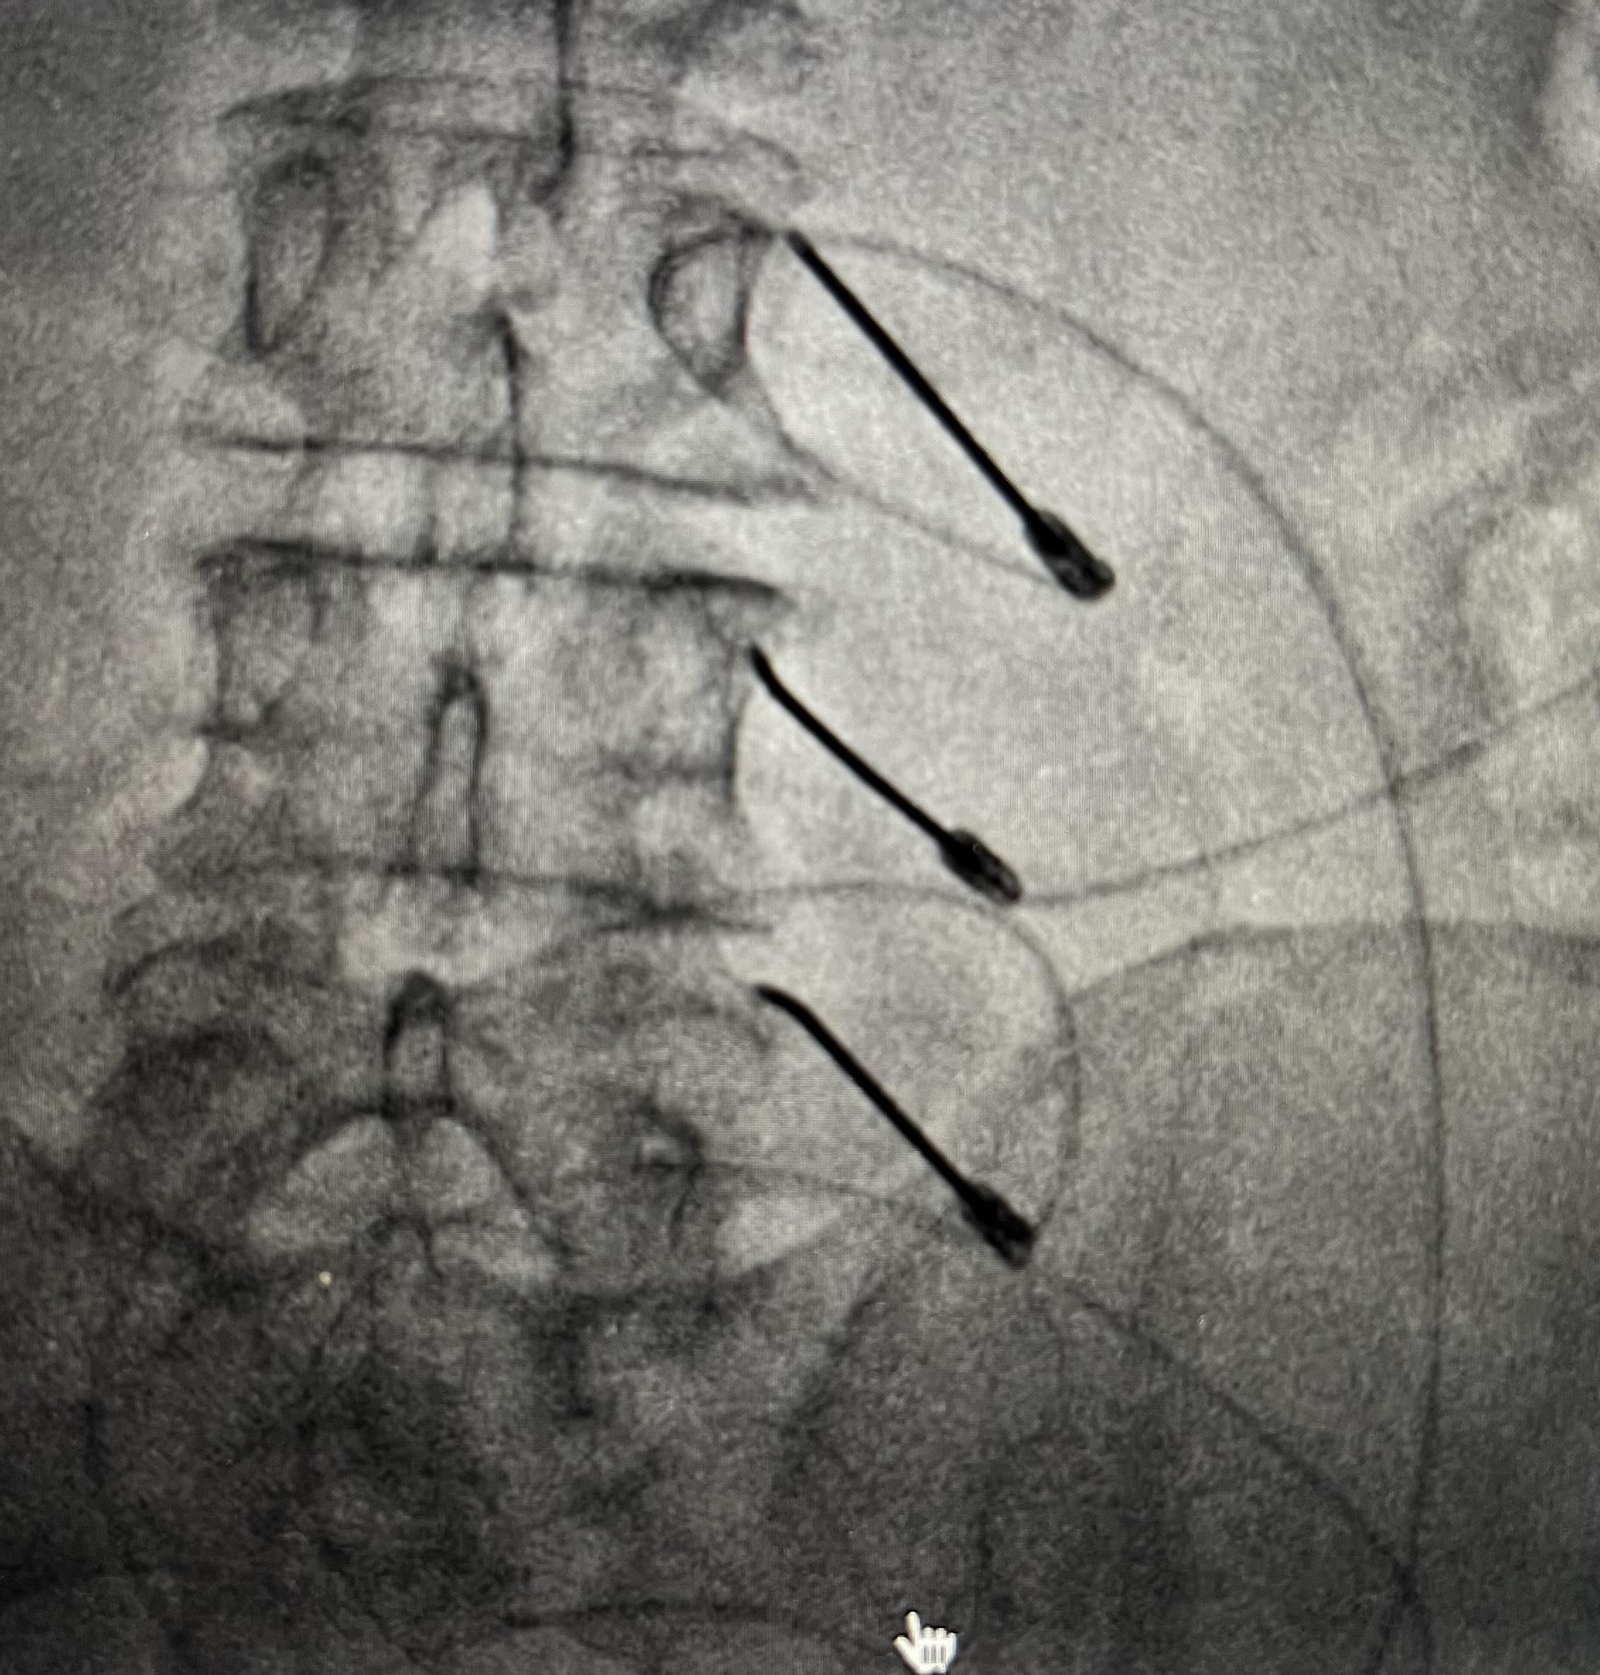

La Rizolisis lumbar es uno de los mejores tratamientos para esta zona del cuerpo.

La Rizolisis lumbar es uno de los mejores tratamientos para esta zona del cuerpo. / D.A.

Se realiza mediante una aguja que se sitúa cerca del nervio responsable del dolor gracias al uso de ecografía o radiografía. Esa aguja puede emitir dos clases de energía:

• Radiofrecuencia continua: la punta de la aguja se calienta hasta una temperatura de 80º durante alrededor de un minuto y lo que buscamos es lesionar el nervio que se encuentra irritado y activado trasmitiendo señales de dolor sin parar. Se realiza con una sedación muy suave porque el paciente tiene que ayudarnos a identificar el tipo de dolor. Cuando la aguja se calienta es posible que note un incremento de “su dolor” lo que nos garantiza estar en el sitio correcto y procedemos con el tratamiento.

• Radiofrecuencia pulsada: la punta de la aguja se calienta a unos 40º; el objetivo no es lesionar el nervio sino modular el dolor, reducir su intensidad.

1. Se realiza con gran efectividad para el dolor de columna. Diría que es la indicación estrella. El dolor lumbar o cervical debido a la artrosis; ese dolor que impide permanecer de pie, se incrementa al girarse en la cama o provoca una importante rigidez recién levantados.